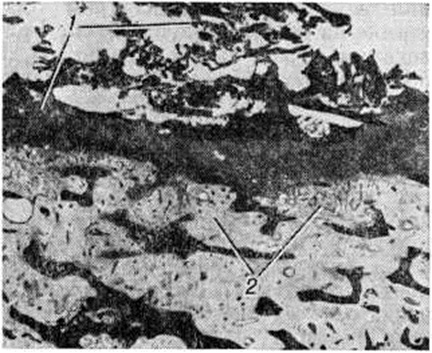

В других случаях наблюдается инкапсуляция гнойников в кости. К 3—4-й недель от начала заболевания при рентгенологическое исследовании на фоне рарефикации определяются очаги некроза кости, поскольку омертвевшая кость не подвергается резорбции и сохраняет прежнюю плотность. При патологоанатомическом исследовании участки некроза выявляются ещё раньше. В дальнейшем те из них, которые находятся в самом очаге нагноения, подвергаются секвестрации (рисунок 1). Секвестрация (смотри полный свод знаний Секвестр, секвестрация) заключается в отторжении омертвевших участков кости, находящихся в полости гнойника, от окружающей костной ткани. При этом в случае образования секвестра в компактной пластинке на её поверхности в зоне прилегания грануляций возникает и постепенно углубляется секвестральная борозда, а в толще — расширение гаверсовых каналов и слияние их между собой. После того как все костное вещество в указанной зоне растворится, секвестр оказывается свободно лежащим в полости гнойника (цветной рисунок 2 и 3). Секвестры губчатого вещества кости отделяются от остальной её части за счёт растворения прилежащих костных балок, находящихся в зоне грануляций (рисунок 2).

Хронический (вторичный) Остеомиелит, возникающий как дальнейшая стадия затянувшегося воспалительного процесса в кости, характеризуется наличием в ней хорошо отграниченных гнойников, содержащих секвестры. Гнойники окружены секвестральными капсулами — костными разрастаниями в периосте и костномозговых пространствах, расположенными кнаружи от соединительнотканной капсулы гнойников. Секвестральные капсулы имеют одно или несколько отверстий («клоак»), сообщающихся со свищевыми ходами в окружающих мягких тканях. Внутренняя поверхность соединительнотканных капсул гнойников покрыта грануляциями, которые в период ремиссии рубцуются, и продукция гноя прекращается. При экзацербации происходит вспышка гнойного воспаления в кости, сопровождающаяся возобновлением закрывшихся свищей и отхождением вместе с гноем мелких секвестров. При хронический Остеомиелит периостальные костные разрастания часто образуют экзостозы (смотри полный свод знаний) и остеофиты (смотри полный свод знаний) причудливой формы. Компактная пластинка может утолщаться, что ведёт к эбурнеации кости. Одновременно продолжается и рарефикация поражённой кости, особенно выраженная в зоне роста грануляций. При массивном растворении поражённого участка кости говорят о костоеде, воспалительном кариесе. Чередование участков эбурнеации, рарефикации, образование экзостозов создаёт пёструю картину поражения кости и сопровождается её деформацией.